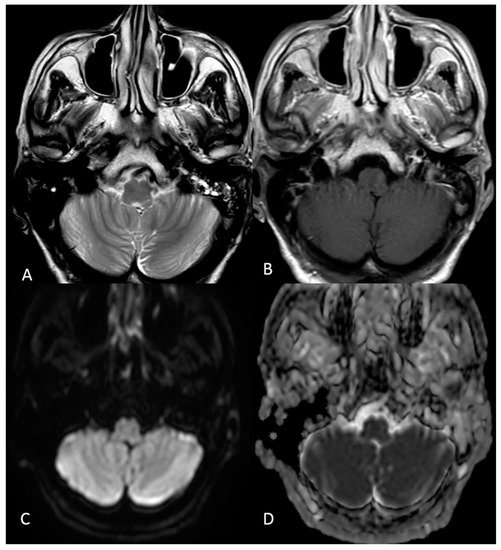

Case Report